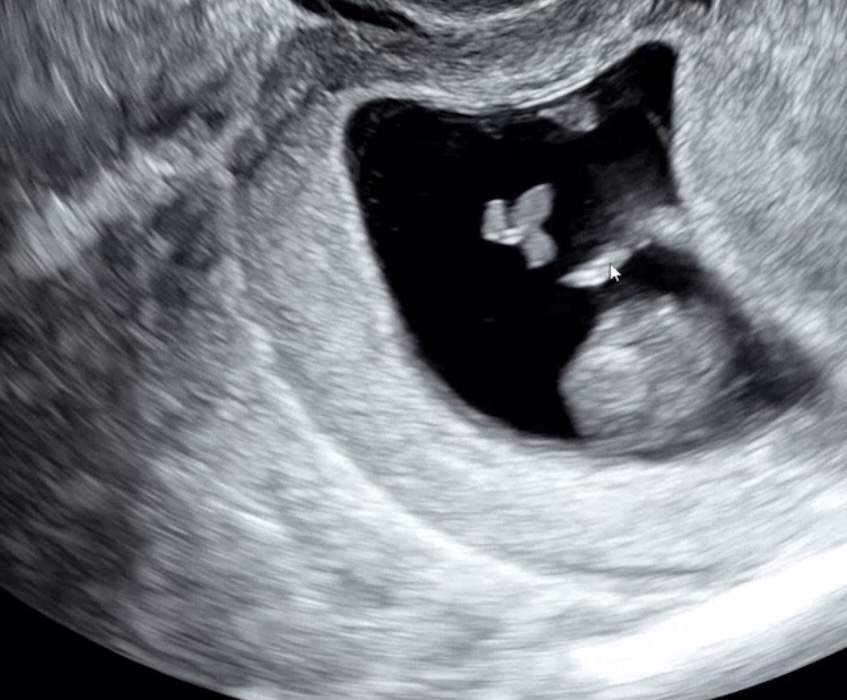

첫째는 건강하게 태어났고 둘째는 작년 7월 선물처럼 찾아와줬지만 끝까지 지키지 못하고 8주차에 떠나보내게 되...